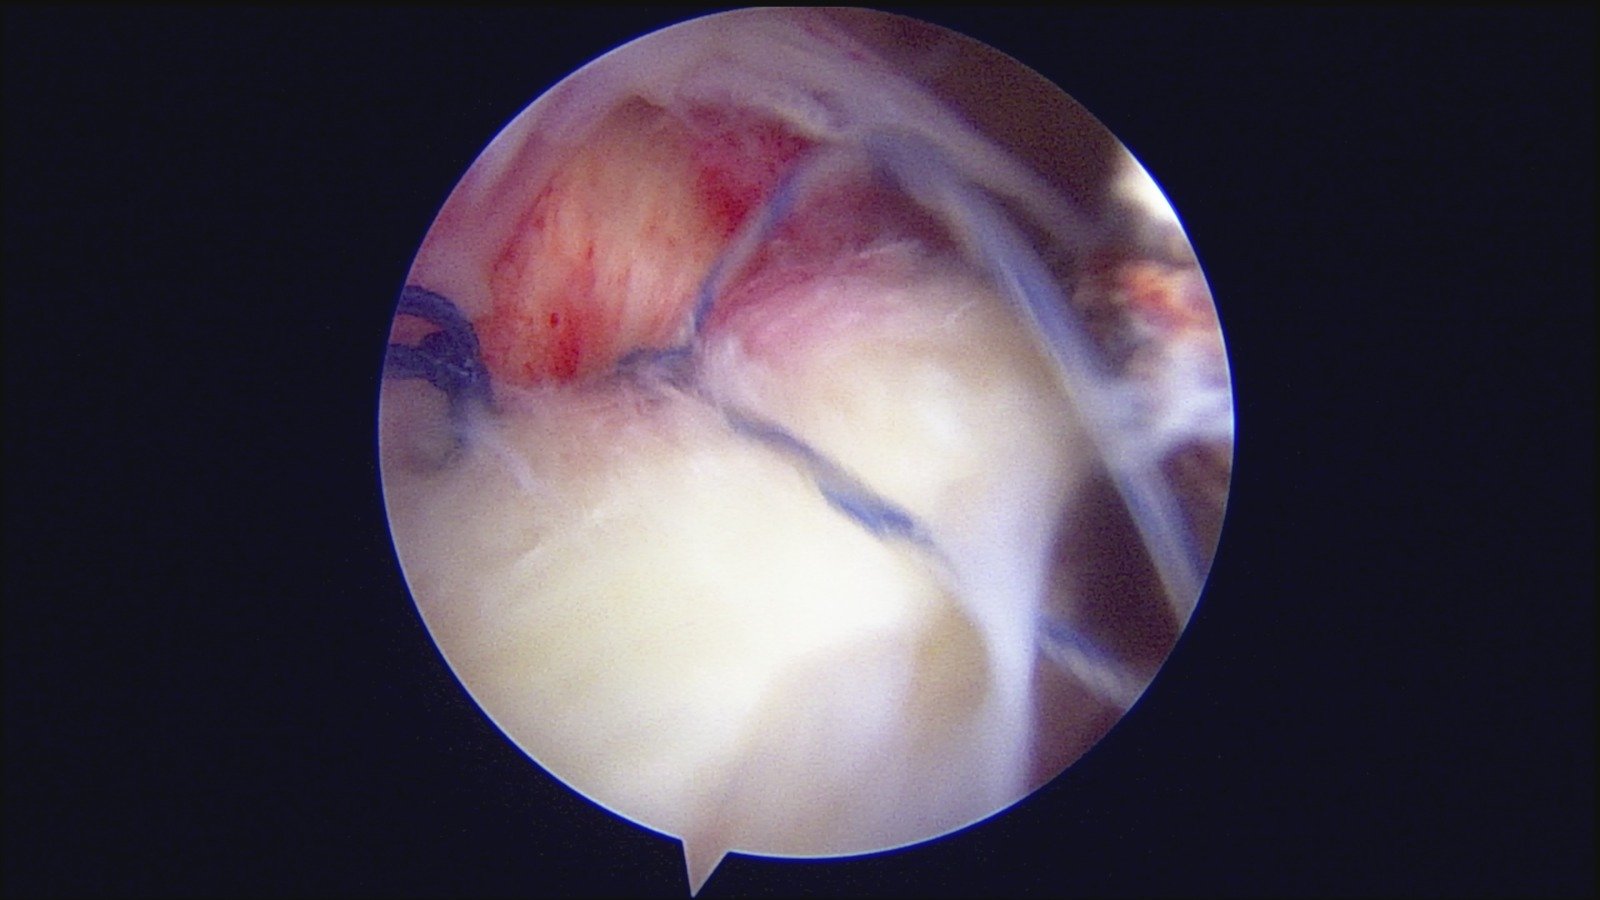

GalleryShoulder rotator cuff repair Meniscus root repair Meniscus repair Bankart repair for recurrent shoulder dislocation ACL reconstruction Machines Instruments